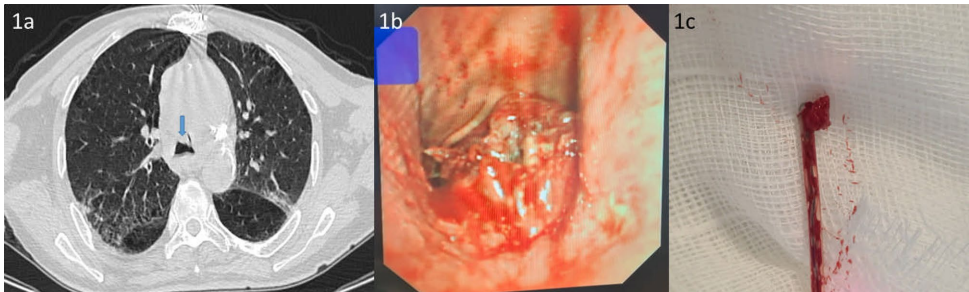

案例1展示77岁男性气管远端病变,在DAPT持续状态下完成7次活检并联用电切术,病理确诊鳞癌。

关键技术方法包括:① 局部应用4℃冷生理盐水和稀释肾上腺素(1:10,000)预防出血;② 使用Fujinon EB-530T支气管镜配合1.8 mm活检钳精确取材;③ 持续心电监护下操作;④ 预先备齐止血球囊、介入放射学支持等应急方案。病例均来自临床急症队列,具有明确的手术指征。

某医疗机构的研究团队在《BMC Pulmonary Medicine》发表的研究,通过3例典型病例的系统分析,为这一临床困境提供了重要见解。研究纳入3例因气道阻塞出现严重呼吸困难的患者,其中2例为冠脉支架术后,1例为外周动脉支架术后,均需持续DAPT治疗。研究团队在完备的止血准备下,使用1.8 mm活检钳实施EBB,所有病例仅出现1级出血(轻度出血仅需吸引),最终均成功获得病理诊断(2例鳞癌,1例肺腺癌复发),未发生严重并发症。